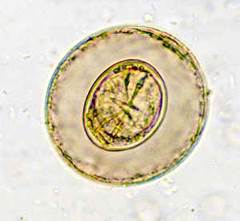

Ascaris lumbricoides, типичная картина яйца в свежих фекалиях Ascaris lumbricoides, яйцо, содержащее личинку